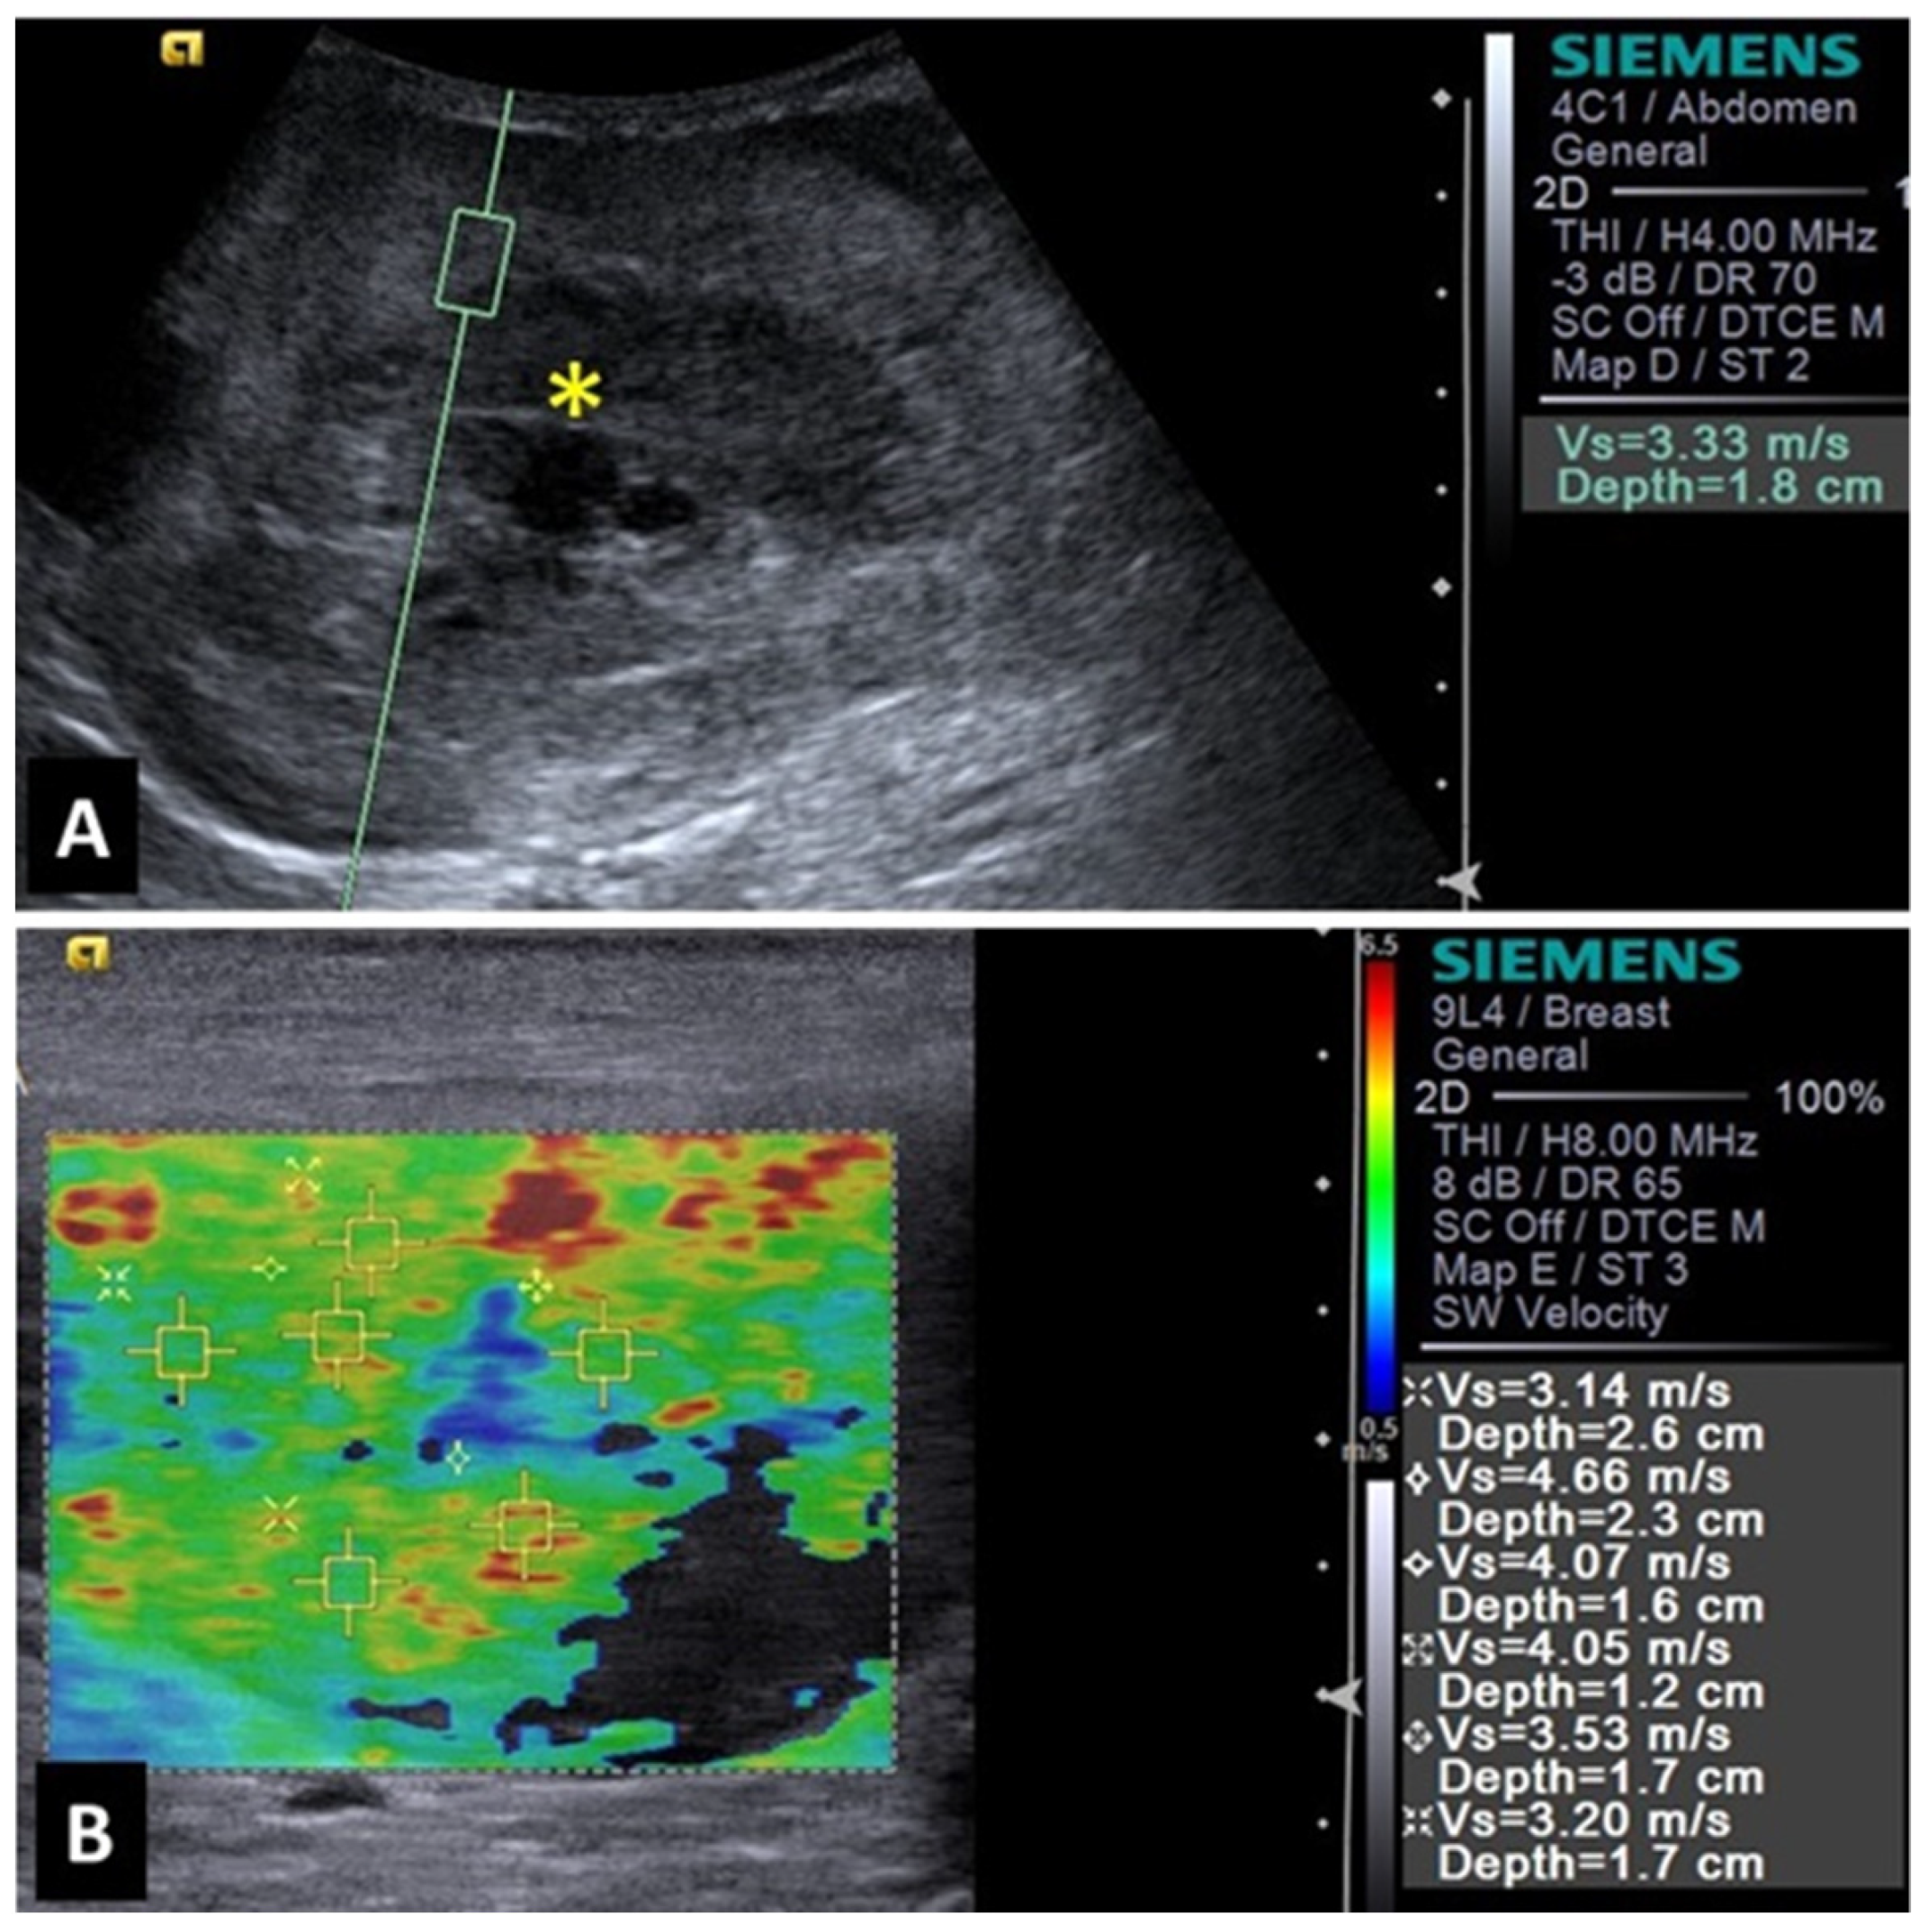

2.5. Liver

- Huaijantug, S.; Yatmark, P.; Phophug, P.; Worapakdee, M.; Phutrakul, A.; Julapanthong, P.; Chuaychoo, K. Quantitative ultrasound elastography and serum ferritin level in dogs with liver tumors. J. Adv. Vet. Anim. Res. 2020, 7, 575–584. [Google Scholar] [CrossRef]